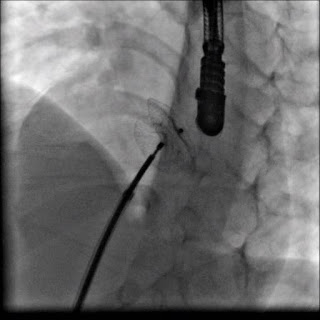

Aşağıda kapatma işlemi sırasında bir görüntü görmektesiniz.